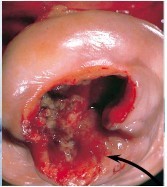

A woman presents to your office for a pap smear after not having one for 10 years. She noticed some bleeding and discomfort with intercourse. Upon exam, you find the following:

Invasive cervical carcinoma

Fully invasive carcinomas are exophytic/ ulcerating, and can be keratinizing or non-keratinizing.

- Can invade adjacent structures (parametrium, bladder, rectum) causing ureter obstruction (–> renal failure) and fistula formation. - Lymph spread to paracervical, hypogastric, external iliac lymph nodes